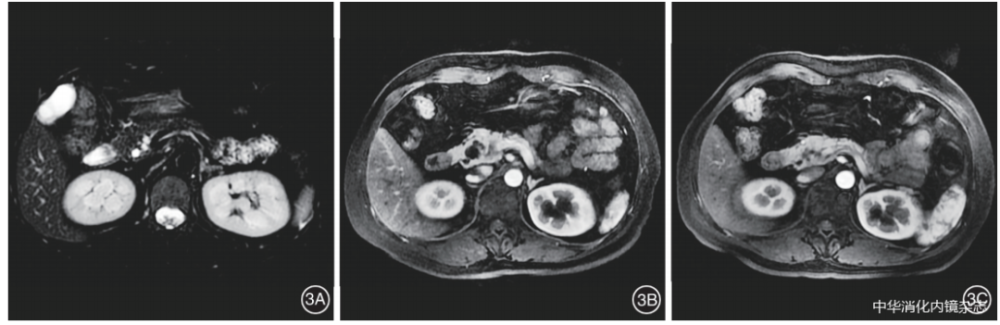

图3内镜超声引导下聚桂醇消融术后病变部分缓解3A:消融前MRI显示胰头部20.0 mm×18.0 mm囊肿;3B:术后2个月复查MRI,囊肿缩小至13.0 mm×12.0 mm,进行第2次消融;3C:第2次消融后13个月随访,MRI显示囊肿缩小到9.0 mm×7.0 mm